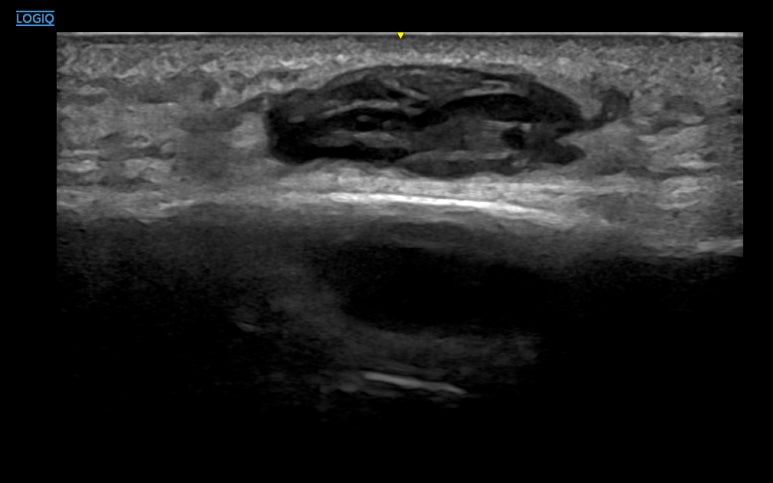

doi.org/10.2214/AJR.19.22752 혈종이 생긴 지 하루 된 것부터 최대 180일까지의 사례들을 분석한 결과, 이 기간 내에 발생한 것이라면 혈종의 '나이'가 시술의 성공 여부를 결정짓지는 않았습니다.

초음파상 피가 굳어 보이는 고에코 상태나 복잡한 격막이 관찰되더라도, 80% 이상의 사례에서 성공적으로 배액이 가능했던거죠. 배액술을 받은 모든 환자가 즉각적인 증상 호전을 보이기도 했고요. * * * ## 2가지 논문을 종합해본 결과즉, 6개월까지는 몸이 스스로 해결하려고 노력하는 기간이자 비침습적으로 해결할 수 있는 ## 이상적인 치료 기간인 셈입니다. * * * ## 5. 한의 초음파의 핵심경혈 주변을 정밀하게 타겟팅! 한의학에서는 이런 혈종을 치료할 때 '경혈' 주변의 해부학적 구조를 면밀히 살핍니다. 초음파를 통해 주변 근육인 경근(經筋) 조직의 손상이나 혈종의 정확한 깊이를 확인하는 것이죠. [하지부] 허벅지의 복토혈(伏兎) 엉덩이의 환도혈(環跳) 과 같은 주변에 깊숙이 자리 잡은 혈종은 손으로 만져서는 정확한 위치를 알기 어렵습니다.